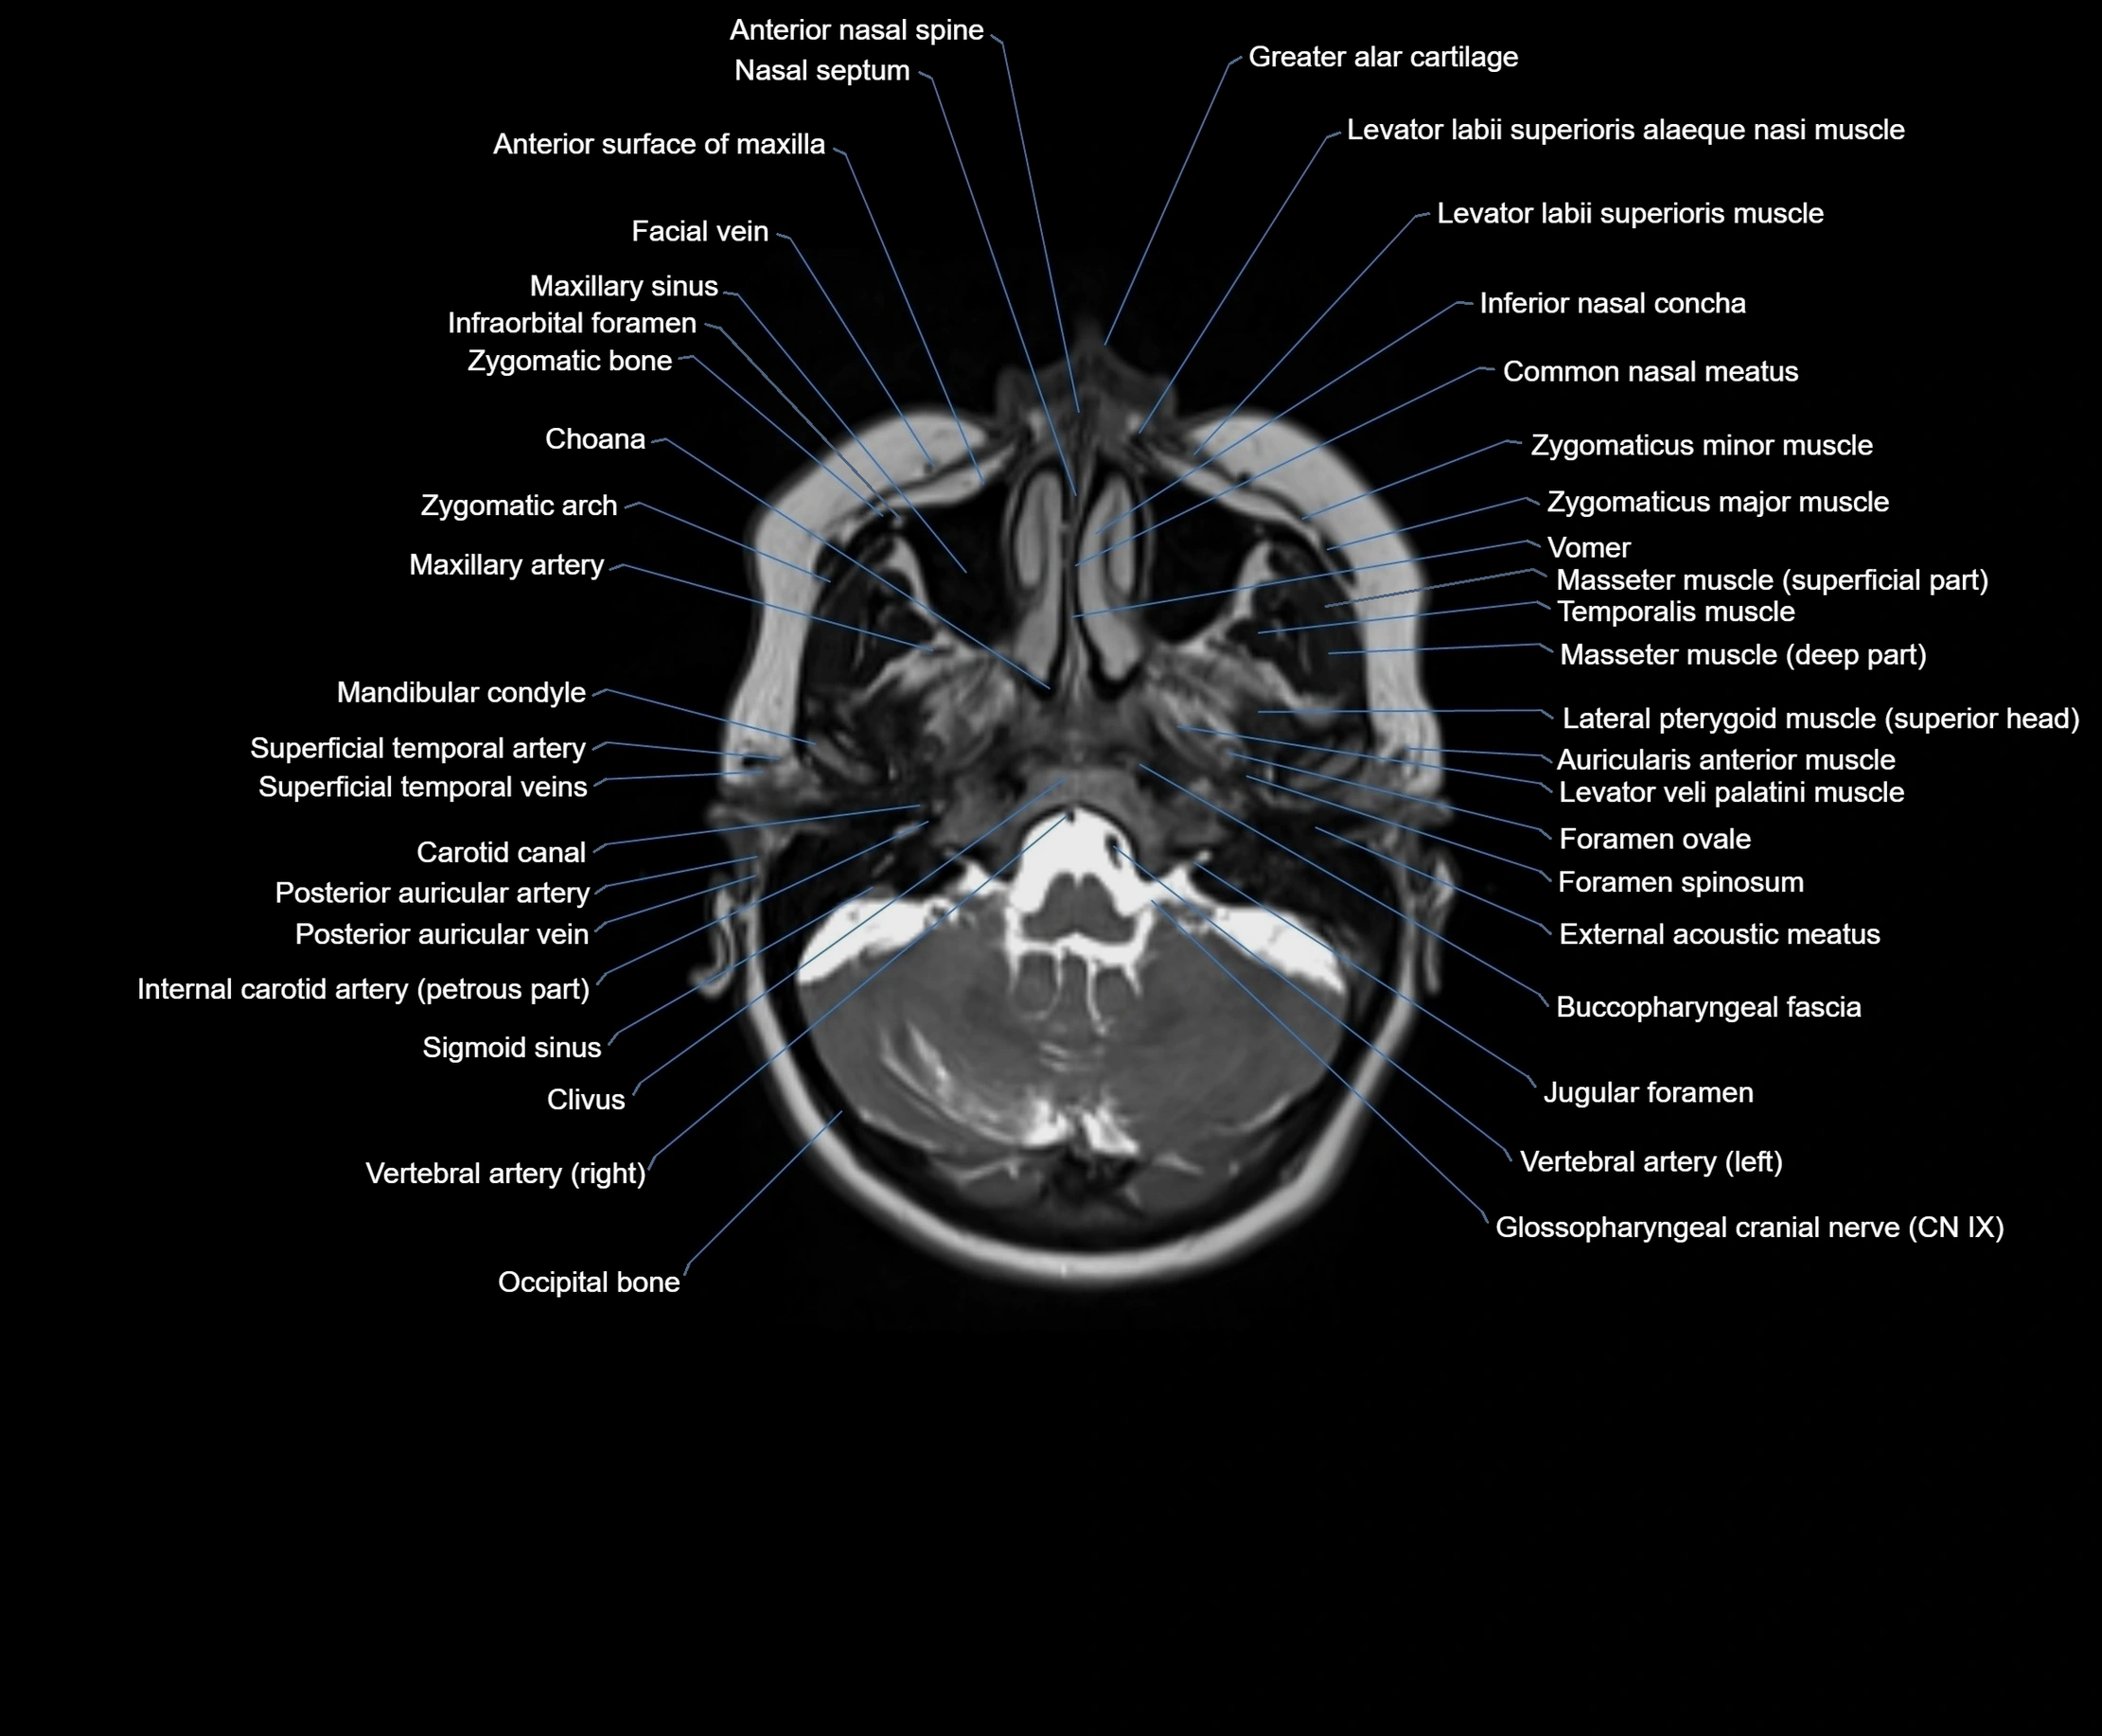

- Anterior nasal spine

- Buccopharyngeal fascia

- Carotid canal

- Choana

- Clivus

- Common nasal meatus

- External acoustic meatus

- Facial vein

- Foramen ovale

- Foramen spinosum

- Glossopharyngeal nerve (Cranial nerve IX)

- Greater alar cartilage

- Inferior nasal concha

- Internal carotid artery (petrous part)

- Jugular foramen

- Levator labii superioris alaeque nasi muscle

- Levator labii superioris muscle

- Levator veli palatini muscle

- Mandibular condyle

- Maxillary artery

- Maxillary sinus

- Occipital bone

- Posterior auricular artery

- Posterior auricular vein

- Pterygoid venous plexus

- Salpingopalatine fold

- Superficial temporal artery

- Superficial temporal vein

- Temporalis muscle

- Vomer

- Zygomatic arch

- Zygomatic bone

- Zygomaticus major muscle

- Zygomaticus minor muscle